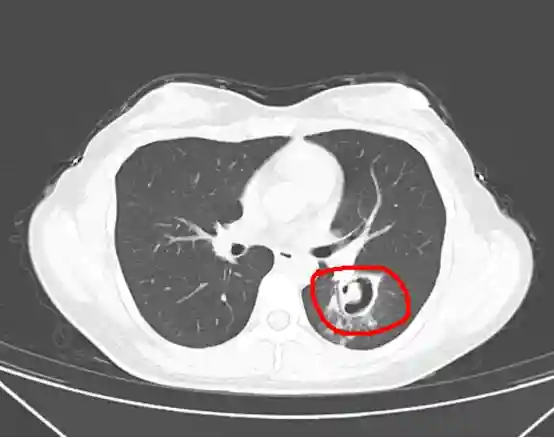

接诊医生从肺部CT上发现,王女士的肺部长出了一个个“小树芽”,怀疑是霉菌性肺炎。

为了进一步确诊病情,周翔为王女士做了纤维支气管镜检查,果然发现气道壁上缀着大量白色菌斑,化验后确认是曲霉菌。